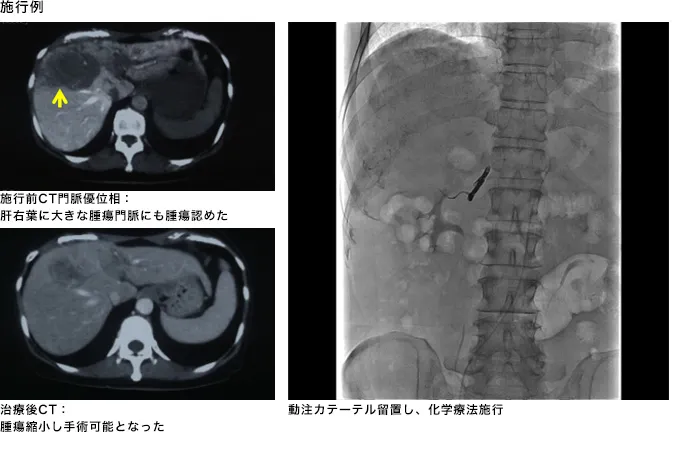

肝動脈リザーバー併用下肝動注療法(HAIC)

肝動脈リザーバー併用下肝動注療法(HAIC)は、肝細胞がんを養う動脈に抗がん剤を注入する治療法です。高濃度の抗がん剤を直接投与することができるので効果が大きくなると同時に、同じ薬を静脈注射して全身投与する場合に比べて抗がん剤の総量は少なくて済むため、副作用が少なくなるメリットがあります。

肝動脈塞栓療法(TACE)と同じように、カテーテルという細い管を大腿付け根の動脈から通し、肝動脈まで進めた後、皮膚の下に埋め込んだ小さいタンクのような器具(ポート)に接続し、埋め込みます(図)。抗がん剤は、週に5回程度の頻度で、このポートに注射針を刺して注入します。埋め込みとはいえ、針を抜いてしまえば外見上はポート部の皮膚が多少盛り上がる程度で、普段通りの生活をすることが可能です。

図 肝動脈内注入化学療法

この治療法の適応となる患者様:

TACE等が適応にならない、がんがより進行した患者様となります。

効果について:

がんがより進行した患者様が対象となるため、従来までは治療したとしても奏功する(腫瘍が小さくなる)確率が30%程度、治療開始からの平均生存期間は12ヶ月前後と言われておりました。

現在では従来使用されている抗癌剤の組み合わせの内容を変えたり、投与方法の工夫をしたりすることで、奏功率が60-80%、治療開始からの平均生存期間は30ヶ月程度と驚くべき効果を認めたと報告している施設もあります。